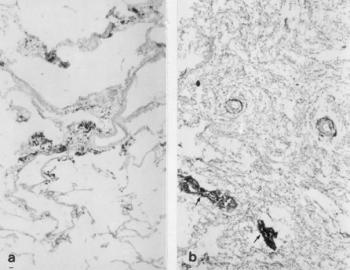

140. ábra. Emphysema és anthracosis 71 éves férfi múmiájának tüdejében. HE festés Idült tüdőtágulat és vaslerakódás (nyíl) 72 éves, 18. századi férfi múmia tüdejében Berlinikék-reakció, eozin kontrasztfestés. Mindkét kép 100× nagyítás

A 18–19. században elhunyt, valamennyi mumifikálódott tetemben találtunk anthracosist, függetlenül attól, hogy életében milyen társadalmi réteghez tartozott (140. ábra). A szén(korom-) ártalom viszonylag enyhe elváltozás, jelentőssé akkor válik, ha egyéb légzőszervi betegség (idült tüdőtágulat, porártalom, tuberculosis) is társul hozzá. A világítási, fűtési technika nemcsak korommal, hanem mérgező gázokkal, korpuszkuláris részecskékkel is telitették a lakóhely levegőjét.